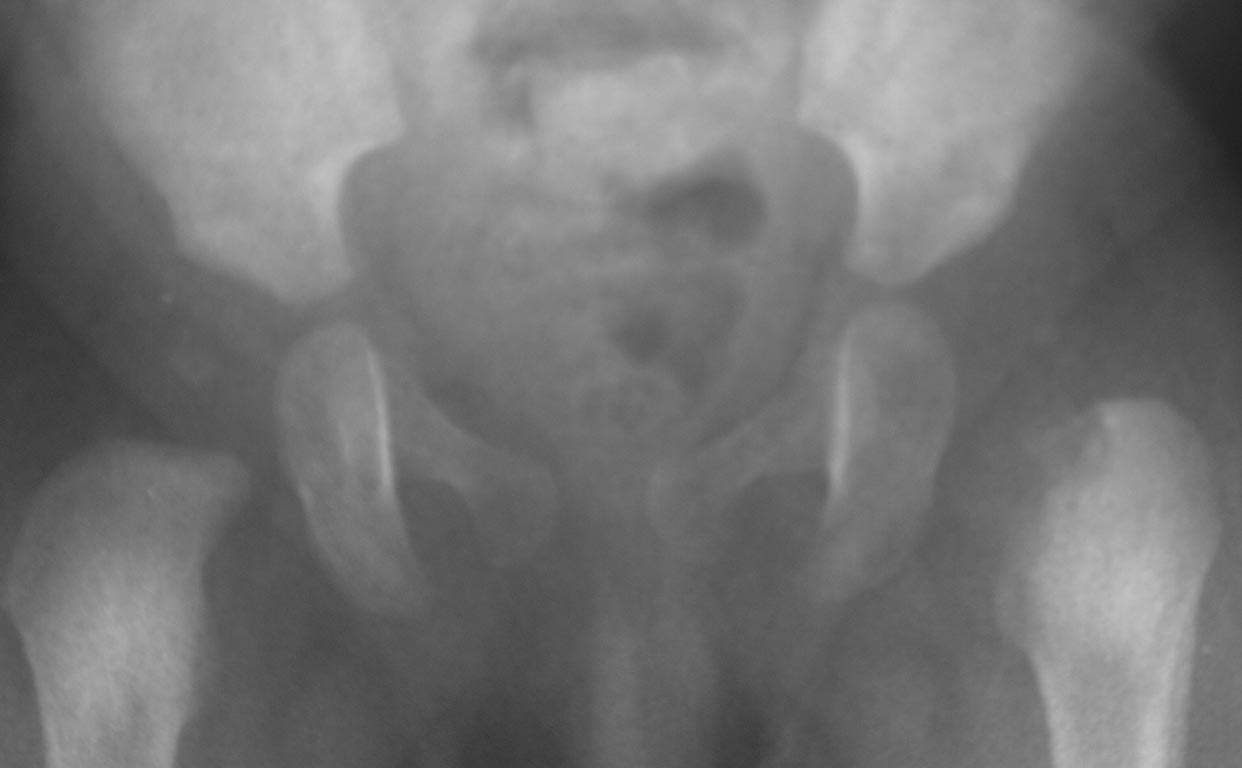

Добрый вечер уважаемые коллеги. Помогите советом, в какую клинику и к

кому обратится с данной проблемой( у ребенка в возрасте 1мес.

диагностирован гематогенный остеомиелит головки бедра). Лечили

консервативно( выписку и фото в динамике прилагаю). На сегодняшний день

ребенку 11 мес. Детские ортопеды по месту сомневаются в тактике( в плане

операции или выжидательная тактика). Хотелось проконсультироваться с

теми кто занимается этой проблемой. Заранее спасибо.